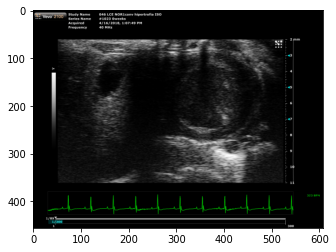

3. Choose and implement a machine learning model: There are various machine learning algorithms that can use to build our model. We used a CNN with an input size of 256x256.

4. Train and evaluate the model: It was trained it using the data that was obtained splitting each frame from it video that had collected. This involves feeding the model the data and adjusting the model's parameters to improve its performance. It was needed to evaluate the model using various metrics to determine how well it performs.

The final model gets a 94% of accuracy.